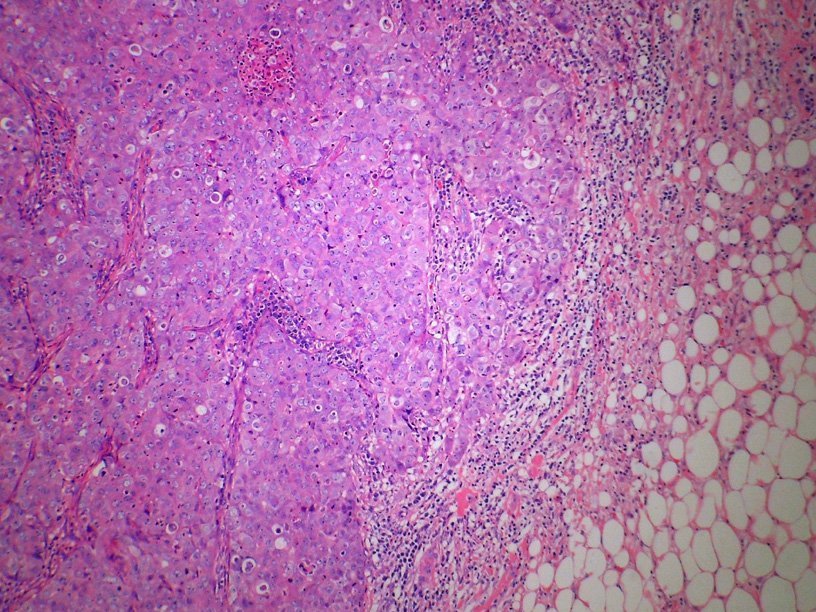

Клетки карциномы молочной железы Wikimedia Commons Еще советским алкоголикам был известен препарат «Антабус», с помощью которого пытаются с большим или меньшим успехом лечить алкогольную зависимость. В ходе применения этого препарата было замечено, что он проявляет противоопухолевые свойства. И лишь сейчас стал ясен механизм его воздействия на опухоль.